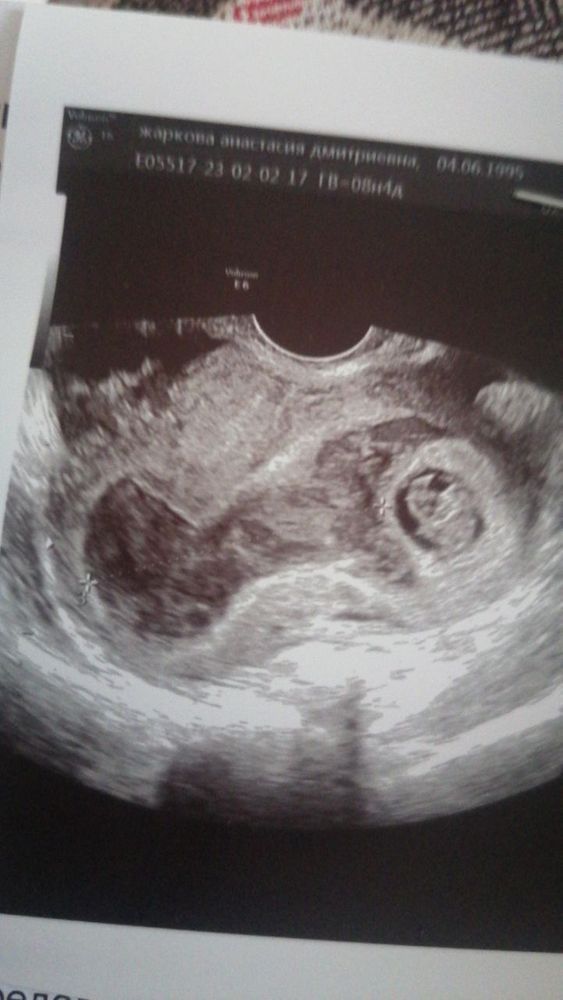

Сегодня было бы ровно 12 недель беременности...

Zima, на узи до беременности ставили только матку с загибом кзади и все. А к беременности мы готов лись, я и на узи ходила и на фолликуломктрии. Просто матка раскрыла свою истинную сущность лишь увеличившись...